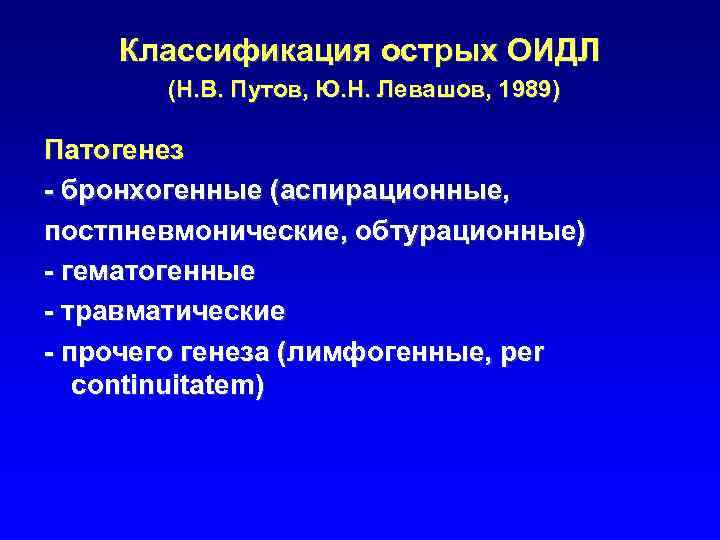

Классификация острых ОИДЛ (Н. В. Путов, Ю. Н. Левашов, 1989) Патогенез - бронхогенные (аспирационные, постпневмонические, обтурационные) - гематогенные - травматические - прочего генеза (лимфогенные, per continuitatem)